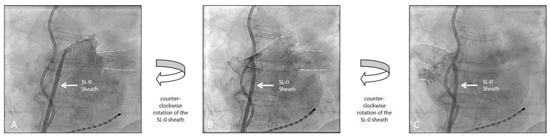

2.2. Pulmonary Vein Visualization and Cryoballoon Guidance